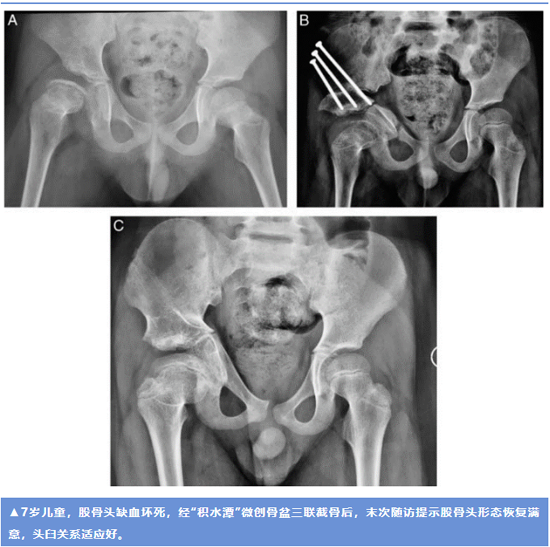

本研究总共纳入43例患者,22例为儿童髋关节发育不良,21例股骨头缺血坏死,采用“积水潭”微创术式,经平均38个月的随访,所有患儿的髋臼指数、中心边缘角、外移指数均明显改善,股骨头包容好,除5例发生无症状坐骨不愈合外,所有病例均未出现严重并发症,手术时间和术中出血量明显缩短。这一随访结果提示该项技术可以显著简化骨盆三联截骨的手术过程,能够使髋关节周围的复杂截骨更为安全、有效和微创。“积水潭”微创术式的提出,也为儿童严重髋关节畸形的保髋手术提供了一种更为友好、可行的解决办法。